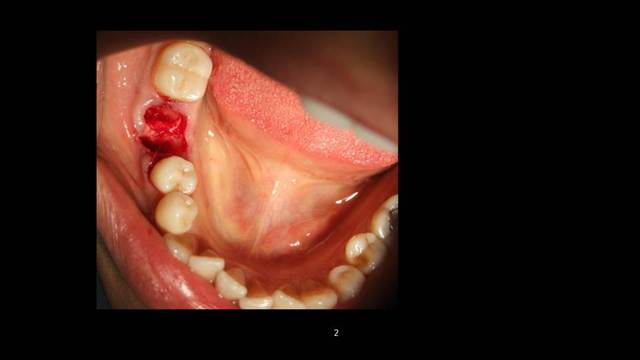

Cookie Consent byPrivacyPolicies.comInsertion immediate au niveau de 46 dans le septum - Eugenol

Insertion immediate au niveau de 46 dans le septum

Mais tu aurais attendu 10 jours que la muqueuse se referme et tu pouvais avoir une jolie gencive attachée à déplacer en vestibulaire, ce qui fait défaut ici ...